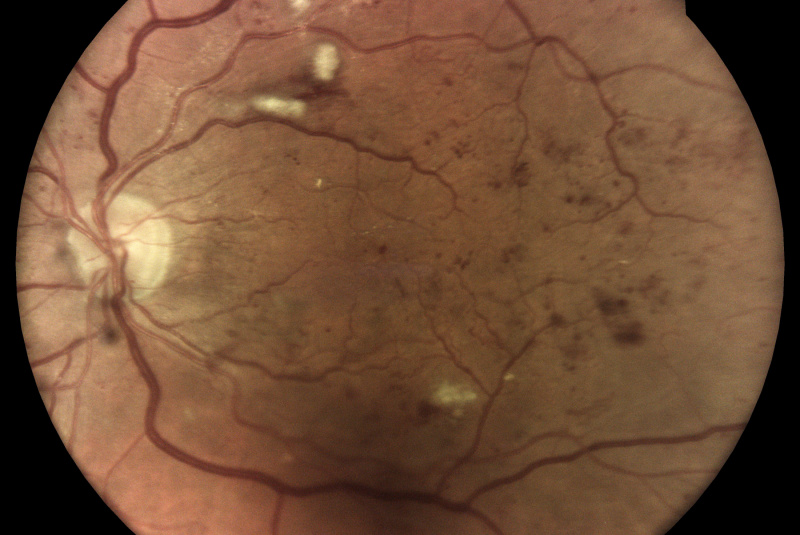

Technologie TrueColor Confocal společnosti iCare překonává limity běžných zařízení pro zobrazování fundu a SLO (scanning laser ophthalmoscop) tím, že kombinuje nejlepší výhody obou. Jednoduše řečeno, fundus kamery poskytují vysokou barevnou věrnost a SLO systémy vytvářejí vysokou ostrost, jasnost, celkovou přesnost a detailnost snímků. Když se tyto vlastnosti zkombinují, vznikne špičkový obraz sítnicové krajiny ve věrných barvách.

Pro diagnostiku a sledování běžných patologií, jako je diabetická retinopatie, musí být zařízení pro zobrazování očního pozadí schopna kombinovat vysoké rozlišení, vysoký kontrast a vysokou barevnou věrnost. To umožňuje zachytit drobné rysy a detaily a rozlišit jednotlivé změny, které byste jinak mohli snadno přehlédnout. Zatímco standardní systémy SLO mají vysokou jasnost, ostrost a kontrast, tradiční fundus kamery nabízejí vysokou barevnou věrnost, běžná zobrazovací řešení tyto dvě věci nekombinují!

Monochromatické lasery používané ve standardních SLO systémech mohou díky konfokálnímu optickému mechanismu poskytovat vysoce ostré a kontrastní snímky. Na druhou stranu však nedokážou zachytit sítnici v jejích skutečných barvách.

Systémy pro zobrazování fundu vytvářejí snímky přirozených barev pouze tehdy, pokud používají bílé světlo: to znamená, že v osvětlovacím paprsku používaném k zobrazení sítnice jsou přítomny všechny vlnové délky viditelného spektra. Na získaném snímku lze rozlišit různé barevné detaily.

Naproti tomu systémy využívající monochromatické zdroje světla, jako jsou systémy SLO, používají k osvětlení sítnice pouze určité vlnové délky. Poskytují proto pseudobarevné obrazy, které postrádají některé spektrální složky, a výsledkem jsou chybějící informace nebo barevné artefakty.

Systém iCare se vyznačuje použitím bílého LED světla v kombinaci s konfokální optikou, což pomáhá získat vysoce kvalitní snímky sítnice se zvýšenou barevnou věrností.